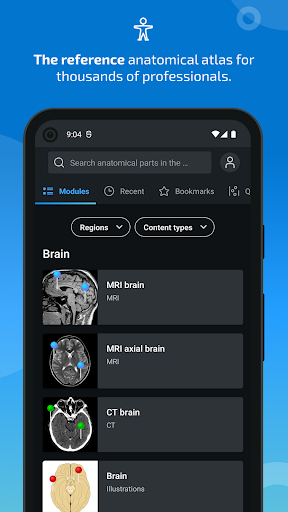

- Desplácese por los conjuntos de imágenes arrastrando el dedo

- Acerque y aleje el zoom

- Toque las etiquetas para mostrar las estructuras anatómicas

- Seleccione las etiquetas anatómicas por categoría

- Localice fácilmente las estructuras anatómicas gracias a la búsqueda de índice

- Múltiples orientaciones de pantalla

- Cambie de idioma con solo tocar un botón